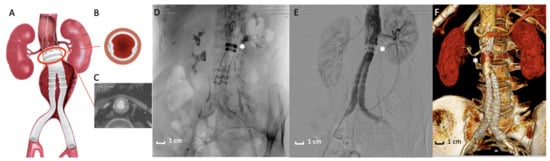

Figure 3. Ovation stent graft. (A) Picture of the Ovation endograft. Proximal sealing is assured by polymer filled O-rings (red circle) adapted to the aortic neck anatomy. (B,C) Details of the axial appearance of O-rings well-opposed to the aortic wall. (D) Intraoperative image of the Ovation stent graft deployed. The asterisk (*) highlights the polymer filled O-rings. (E) Angiographic acquisition that reveals the good exclusion of the AAA by the polymer filled O-rings (*). (F) 3D volume rendering of Computed Tomography Angiography at 3-months follow-up that shows the correct exclusion of the AAA. The asterisk (*) indicates the polymer filled O-rings located in the proximal fixation zone.

A few years later, an evolution of the Enovus was proposed for human application with the name of Ovation Endograft (Endologix, Irvine, CA, USA). After successful animal investigations [72], the platform was tested in clinical trials with positive feedback, which was a fundamental evolution in the use of polymers in the EVAR field. The endograft is based on a new concept design separating fixation from sealing—fixation activity is assured by a suprarenal stent and anchors (not different from traditional suprarenal EVAR devices), while sealing activity is based on inflatable O-rings filled with a low-viscosity, non-embolic, radiopaque fill polymer instead of traditional self-expanding stent grafts. The adaptability of the proximal O-ring filled with polymer to the patients’ aortic neck anatomy determines a substantial increase in EVAR feasibility [73,74]. In other words, polymer injected in the O-rings creates a customized circumferential sealing at the proximal aneurysmal neck level, without executing any outward pressure on the aortic neck wall once the final deployment is completed. This assumption comes with a benefit in reducing aortic neck dilatation and consecutive endograft migration, a typical complication of SESGs. All these features define the revolutionary concept of “Custom Seal” as a tailored adaptation of polymer rings to the aortic wall, including wall calcification, wall thrombosis, and aortic tortuosity [75,76,77].

The importance of polymer in the proximal endograft zone is even greater in the exploratory experience of the use of the Ovation endograft in the treatment of patients with Juxtarenal-AAA (those aneurysms involving the infrarenal abdominal aorta adjacent to or including the lower margin of renal artery origins [87]) and is unfit for traditional open surgery repair of Fenestrated-EVAR. In these particular cases, the endograft is deployed, letting the sealing ring land very close to the lowermost renal artery (Figure 3A,E,F) [88,89]. The correct deployment assures the stability of this implant of the endograft and, in particular, by the sealing activity of polymer rings, including the O-ring capability to adapt to irregular anatomies.